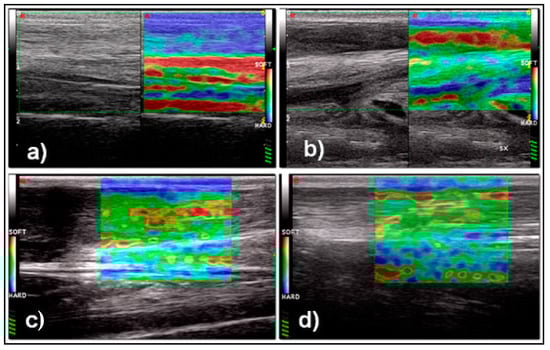

| Mean +/− SD Elx-t%hrd | 89.9 +/− 15.3 | 40 +/− 25.1 (*) | 31.8 +/− 19 (†) | 47.2 +/− 29.1 (§) |

| Mean +/− SD Elx-t%sft | 9.9 +/− 15 | 67.4 +/− 26.4 (*) | 52.8 +/− 29.5 (†) | 69.6 +/− 19.2 (§) |